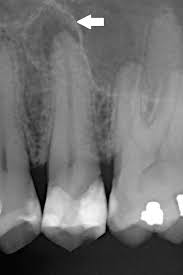

4. X-레이 검사: 치주염 진단에는 치아 주변 뼈의 손상 정도를 평가하기 위해 X-레이 검사가 사용될 수 있습니다. 이를 통해 의사는 뼈 손상이 어느 정도인지 확인하고 치주염의 정확한 진행 정도를 평가할 수 있습니다.